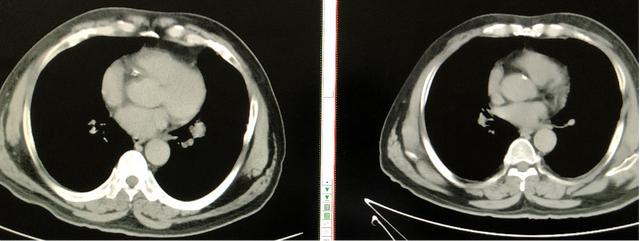

50岁的大爷,因咳嗽、咳痰就诊于南昌市第三医院, 查胸部CT:发现左下肺肿物,伴4R、5、7纵膈淋巴结肿大。支气管镜提示:肺腺癌。临床分期:cT1N3M0,IIIb期。

放疗结束后复查胸部CT提示肺部原发灶及纵膈转移淋巴结明显消退,放疗效果明显。

放疗后隆突下淋巴结明显消退

放疗后左下肺肿块完全消退